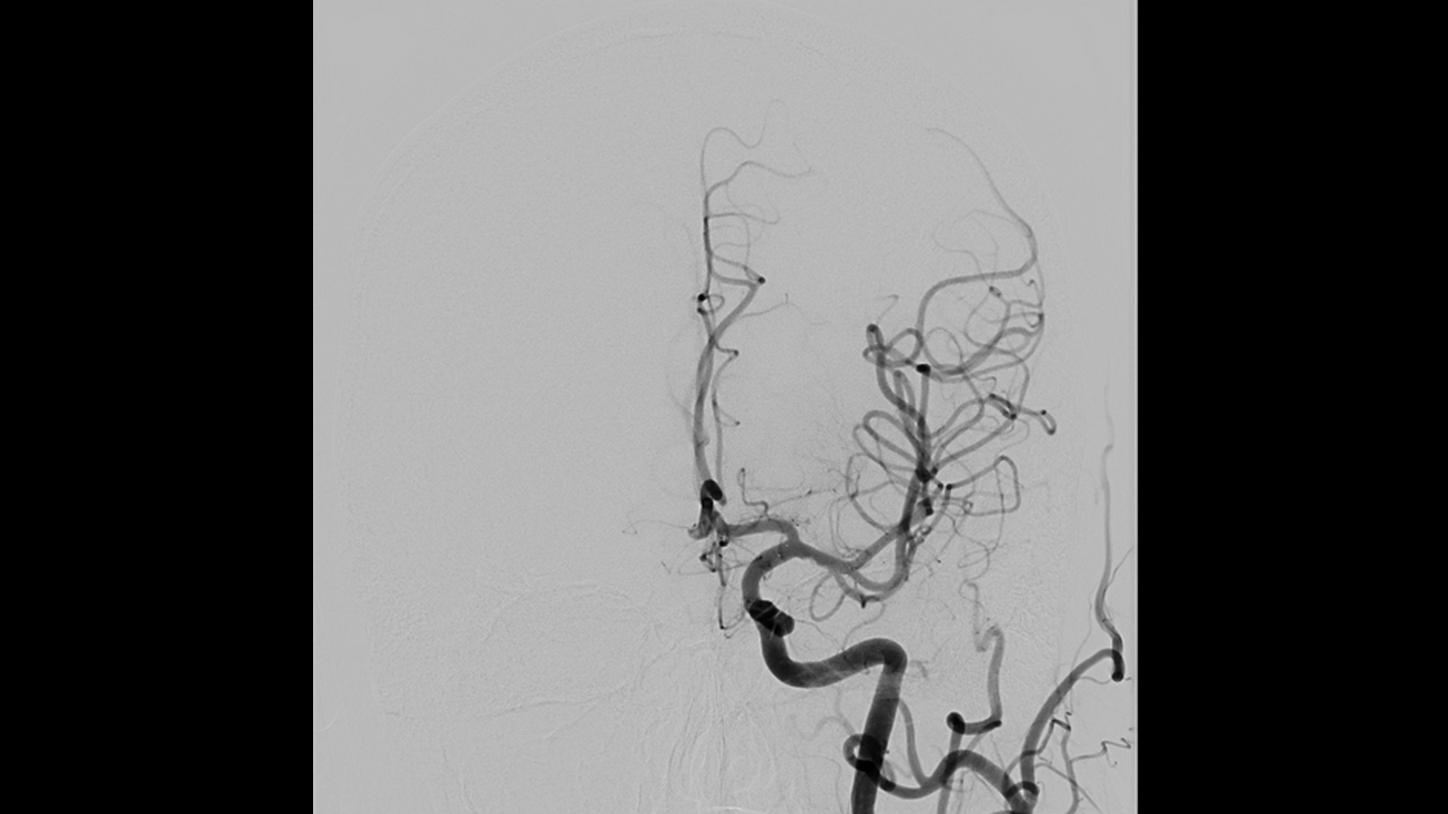

A new approach to image quality and dose in minimally invasive interventions

During a procedure, interventionalists and surgeons have to see clearly – while keeping dose as low as possible. Based on big data, OPTIQ delivers constant image quality throughout a procedure, independent of angulation or patient size1,2, while also significantly reducing dose.

Simple and fast 3D imaging, everywhere

Generate 3D acquisitions with excellent spatial and soft tissue resolution whatever your clinical case is. With up to 95°/s rotation speed, ARTIS icono systems can acquire syngo DynaCT images in just 2.5 seconds with fewer motion artifacts and less use of contrast media.3 Simple and fast 3D imaging from head to toe with 200° rotation range gives you confidence in procedure planning.

Precision is key to improve the workflow in complex procedures. The reuse of vessel maps for DSA and 3D Roadmap even after C-arm and table movements speeds up the intervention and reduces dose and use of contrast media. ARTIS icono supports this with a (re)positioning accuracy of better than 0.5 mm.